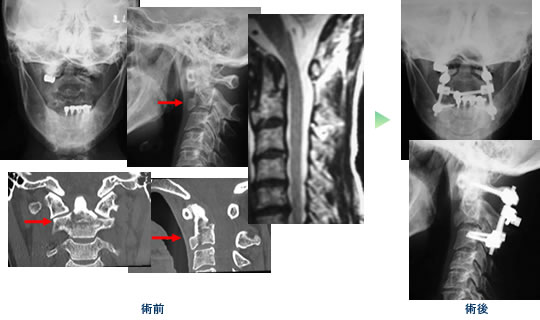

頚椎損傷 (軸椎:第2頚椎骨折)

環軸椎亜脱臼 (環椎部狭窄症)